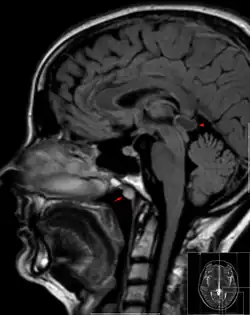

Tornwaldt cyst imaged on sagittal MRI (FLAIR). The cyst appears hyperintense in the midline of the nasopharynx (arrow). In this case there is also a cyst of the pinealis gland (arrowhead) showing a signal intensity slightly higher than the CSF. | |

A Tornwaldt cyst (also spelt as Thornwaldt or Thornwald[1]) is a benign cyst located in the upper posterior nasopharynx. It was first described by Gustav Ludwig Tornwaldt. It can be seen on computed tomography (CT) or magnetic resonance imaging (MRI) of the head as a well-circumscribed round mass lying in the midline. In most cases, treatment is not necessary. Indications for treatment include symptomatic lesions, large lesions (>1 cm), or lesions adjacent to the eustachian tube orifice.[2]